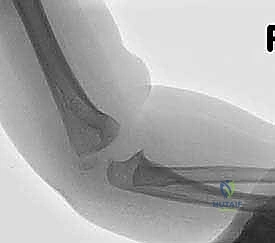

التصوير بالأشعة السينية (X-rays)

الأشعة السينية هي الأداة الأساسية للتشخيص. يتم أخذ صور في وضعيات متعددة (أمامية خلفية AP، وجانبية Lateral، وربما مائلة Oblique).

لماذا الكسر مخادع؟ في الأطفال الصغار، تكون أجزاء كبيرة من مفصل الكوع عبارة عن غضاريف لم تتحول إلى عظم صلب بعد (لم تتعظم). الأشعة السينية لا تظهر الغضاريف، بل تظهر العظام فقط. لذلك، قد يبدو الكسر في الأشعة صغيراً جداً (مجرد قشرة عظمية صغيرة مكسورة)، بينما في الواقع، هناك كتلة غضروفية كبيرة جداً (تحتوي على سطح المفصل وصفيحة النمو) قد انفصلت تماماً وتدور حول نفسها.

هنا تتجلى خبرة الجراح. الطبيب غير المتخصص قد يرى الأشعة ويقول للآباء "إنه كسر بسيط يحتاج لجبس"، بينما الخبير مثل أ.د. محمد هطيف يدرك من خلال النظرية التشريحية وخبرته الطويلة أن هذا الكسر غير مستقر ويحتاج لتدخل جراحي.

ثانياً: العلاج الجراحي (الرد المفتوح أو المغلق والتثبيت الداخلي)

الجراحة هي المعيار الذهبي والأكثر أماناً لأي كسر متحرك (أكثر من 2 ملم) أو الكسر الذي تعرض للدوران (Jakob Stage 2 & 3). الهدف من الجراحة هو إعادة القطعة المكسورة إلى مكانها بدقة ميكروسكوبية وتثبيتها بقوة لمنع حركة العضلات من إزاحتها مرة أخرى، مما يسمح للعظم بالالتئام السليم.